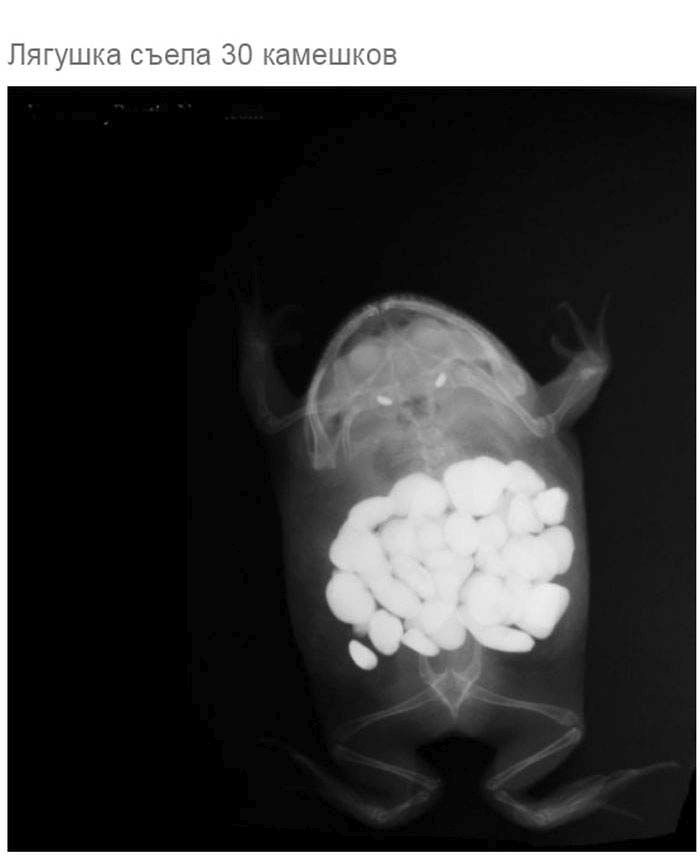

» Что может оказаться в желудке собаки

Что может оказаться в желудке собаки